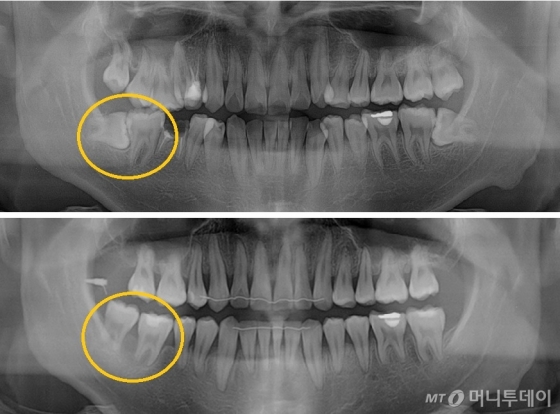

오늘은 임플란트에 대해 포스팅하려고 합니다. 30대 환자분이 사랑니를 뽑으러 강남리온치과를 찾아오셨습니다. 사랑니가 나오는지는 모르겠지만 오른쪽 아래가 아프다”며 먼저 전체 엑스레이를 찍고 확인하기로 했다. 엑스레이를 찍고 나서 오른쪽 아래가 불편한 이유를 깨달았다.

CT분석과 정밀한 플래닝 후 오른쪽 아래 사랑니의 염증을 무시하고 사랑니의 염증으로 인해 앞니 뿌리가 손상되어 녹아내려서 앞니와 앞니를 뽑기로 했습니다. 같이.. 이번 경우는 정말 안타깝네요.. 빨리오면 후회할텐데 어서 사랑니 뽑고 앞니 제대로 안쓰고 살겠습니다. 치아를 지탱하는 잇몸뼈가 튼튼하지 않고, 그 원인은 사랑니에만 국한되지 않는 것 같습니다.

이것은 사랑니와 작은어금니만을 엑스레이로 촬영한 것입니다. 염증이 진행된 지 어느 정도 시간이 지난 것으로 보이며, 염증 초기에는 환자가 별다른 불편함을 느끼지 않는 것 같았으나, 염증이 진행됨에 따라 점차 잇몸뼈가 녹아내리면서 치아가 조금씩 진동하게 되었습니다.

왼쪽의 사랑니와 오른쪽의 앞니. 사랑니 옆에 뿌리가 녹아 짧아지는 것을 보셨나요? 발치가 전혀 아깝지 않은 것이 현 상황입니다. 발치 후 엑스레이 사진입니다. 추출된 공간은 여전히 비어 있습니다. 염증이 없고 잇몸뼈의 상태가 양호하면 발치 당일 임플란트 식립이 가능하나, 이 경우 임플란트가 잘 고정되지 않아 실패할 확률이 높습니다. 사람마다 다르지만 뼈가 완전히 채워지는 데는 일반적으로 1~2개월 정도 걸립니다. 그 기간 동안 환자의 잇몸 상태가 좋지 않아 잇몸 치료를 시작하기로 했습니다. 환자가 항상 알아야 할 것은 치아를 오래 사용하기 위해서는 잇몸이 건강해야 한다는 것입니다. 노화가 진행됨에 따라 잇몸의 노화 과정이 서서히 사라집니다. 잇몸이 건강하면 치아를 지탱하는 잇몸뼈도 건강하기 때문에 잇몸이 좋지 않은 상태에서 치주치료를 지속하는 것이 좋습니다. 재생치료도 잇몸치료와 동시에 진행됩니다. 치아는 송곳니와 어금니 사이에 틈이 있기 때문에 “웃을 때 치아 사이 틈이 보여서 신경이 쓰인다”고 합니다. 수지가 벗겨지고 변색됩니다. 레진을 접착제로 붙이는 과정이기 때문에 칫솔질, 음식물 섭취 등 외부 자극에 의해 색이 진해지거나 사라질 수 있습니다. 다만, 치아가 빠지더라도 발치하지 않고 재수술이 가능하나, 레진치료 후 재수술 비용이 발생하게 됩니다. 공간이 자연스럽게 채워지나요? 위에서 언급한 것처럼 변색과 벗겨짐이 걱정된다면 교정이나 보철로 치료하는 것이 가장 좋다. 치아 사이가 벌어져 고민이시라면 치과에 내원하셔서 전문의와 상담을 받으시는 것이 좋습니다. 레진 전후 비교는 이제 2개월이 되었습니다. 잇몸뼈가 꽉 차 있는지 엑스레이를 찍었습니다. 2개월 전과 비교하면 다행히 뼈가 많이 자랐다. 이제 임플란트 식립이 가능해 당일 식립이 가능합니다. 치근에 해당하는 임플란트 픽스쳐만 식립합니다. 정확한 각도, 깊이 및 위치에 앵커를 설치하는 것이 중요합니다. . 누가 그렇게 좋아. . ^^ 잇몸뼈 상태가 좋지 않은 환자분들은 특히 힘듭니다. 이렇게 되기까지 약 2개월을 기다린 끝에 임플란트 헤드를 들어올리기로 결정했습니다. 2개월 후 치은골이 임플란트와 잘 맞는 것을 확인하고 최종 수복을 하였다. 방금 식립했을 때와 비교하여 X-ray 촬영 결과 주변 치은골이 잘 부착되고 단단해졌습니다. 첨부된 사진은 이식된 크라운의 사진입니다. 크라운 모양도 잘 되어있어요^^ 그리고 가운데 동그란 구멍도 똑같이 보이시죠? 이 구멍에는 임플란트의 뿌리와 헤드를 연결하는 작은 나사가 임플란트에 삽입됩니다. 임플란트 문제로 인해 보철물이 흔들리는 경우 이 구멍을 사용하여 임플란트를 조이는 나사를 조이거나 교체합니다. 임플란트 전보다 오른쪽 치아를 사용할 수 있어 오른쪽에서 편안하게 식사를 할 수 있어 마음이 편하다고 한다. 또한 환자가 몸이 좋지 않은 경우 염증이 이미 증가한 경우가 많습니다. 궁금하신 사항이 있으시면 언제든지 강남리온치과의원으로 연락주시기 바랍니다. 오늘도 좋은 하루 보내시길 바랍니다.서울시 서초구 강남대로 415 대동빌딩 4층 강남리온치과의원